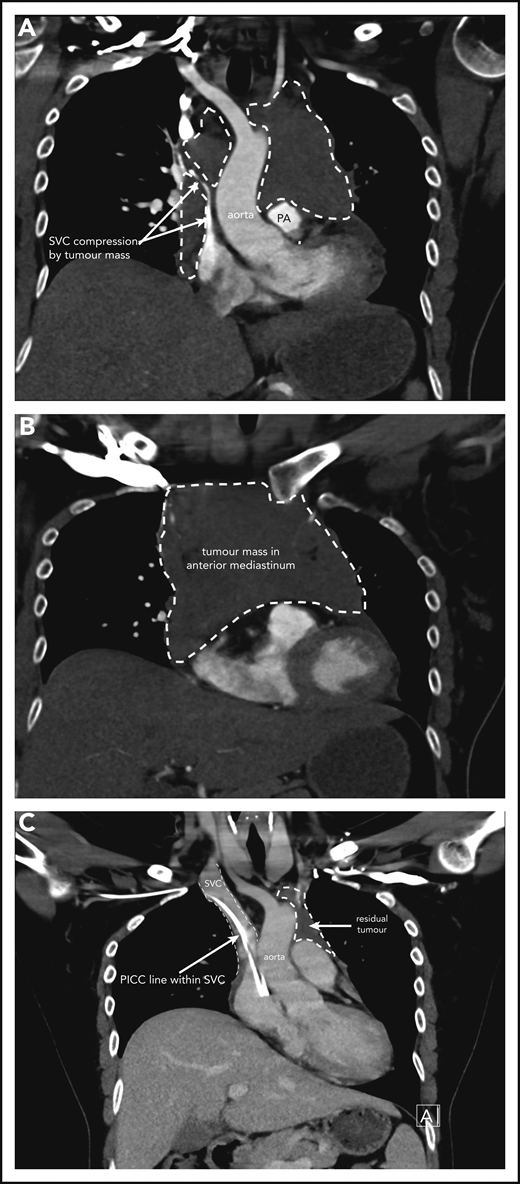

Case 1 of patient with primary mediastinal B-cell lymphoma presenting at 31weeks gestation. (A) Coronal section chest CT scan with contrast at diagnosis, pretreatment. Illustrates significant compression of SVC by tumor mass (within broken lines) on right and demonstrating extent of mass also on left superior to pulmonary artery (PA). (B) Transverse section chest CT scan with contrast at diagnosis, pretreatment. Illustrates extent of anterior mediastinal tumor mass. CT imaging suggested possible moderate-sized pericardial effusion found on echocardiography to be a small effusion. (C) Coronal section chest CT scan with contrast at completion of treatment. Normal caliber SVC with a peripherally inserted central catheter (PICC) line in situ. Small volume of residual tumor (within broken lines). Subsequent PET-CT scan demonstrated no activity confirming a complete metabolic response.

The patient initially received high-dose steroids for treatment of her SVC syndrome once the diagnosis was made. She then received her first cycle of DA-EPOCH-R therapy at 33+3 weeks of gestation and tolerated it very well. Additionally, growth colony-stimulating factor was administered with no complications. An MRI of the chest was performed 2 weeks later and showed reduction in the size of the mediastinal mass to 8.6 × 4.5 × 5.4 cm with significant improvement in SVC and airway compression. Labor was induced at 35+5 weeks, and our patient had an uncomplicated vaginal birth to a healthy girl (birth weight, 2585 g) who had no neonatal complications. She received her second cycle of DA-EPOCH-R on day 22 as per the chemotherapy regimen without complication on the fourth postpartum day and subsequently completed a total of 6 cycles of therapy. CT and FDG-PET scans were done at completion of therapy, showing significant shrinkage of the mass on CT (Figure 1C) and complete metabolic response on FDG-PET, and she did not require consolidation mediastinal radiation. She remains in complete remission at last follow-up.